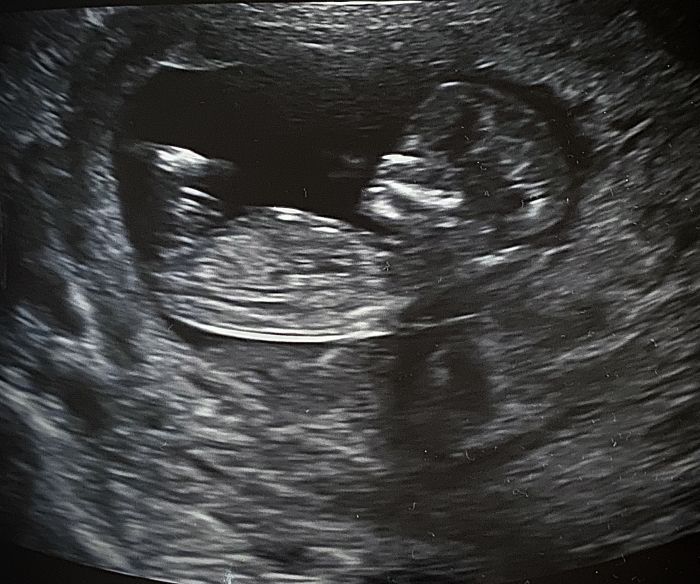

Ahojky holky, taky se hlasim po screeningu :-) nam dopadl super, riziko vyskytu DS v mem veku je 1:940 a nam bylo napocteno 1: 15 500 takze super. Doktor pochvalil, ze mame krasne a prosperujici mimco, takze stres po prichodu rychle opadl :-) manzel byl skvely, mel slzicky na krajicku, protoze zatim z zadneho ultrazvuku to tak hezky vsechno nevidel :-) Doufam a preji uspechy a jen dobre zpravy ze screeningu :-)